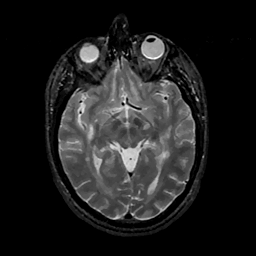

MR Study #11, May 5, 1991 -- Slice #22